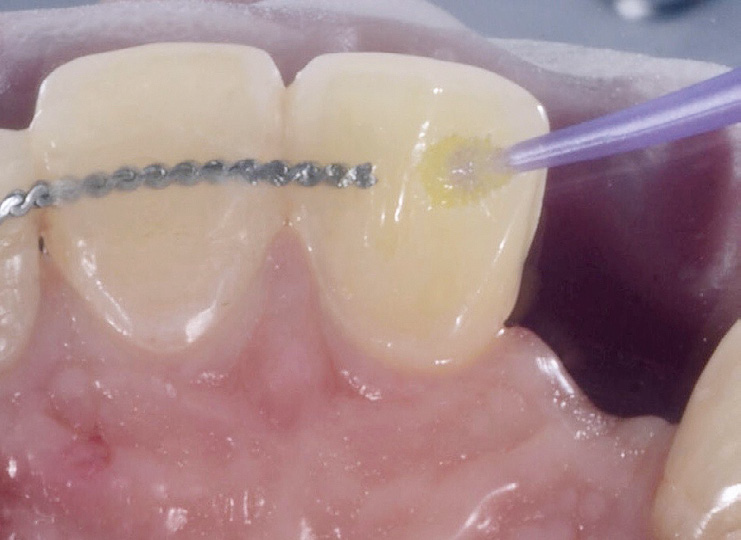

Etching of preparation.